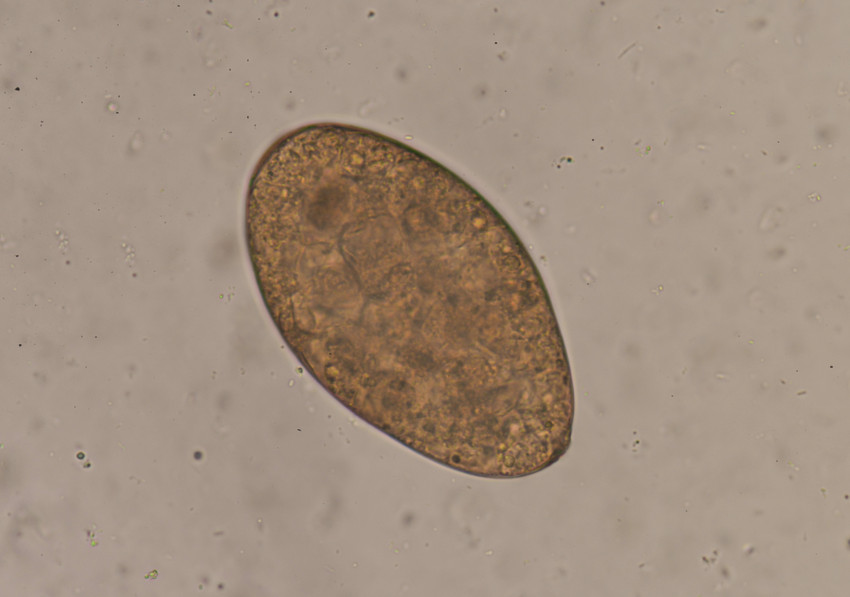

Eitjes, cysten of larven

Het gaat dan om parasieten zoals amoeben en talloze soorten wormen, en dan met name de eitjes ervan. Wanneer bij iemand de aanwezigheid van zo’n parasiet wordt vermoed, levert die persoon een monster in van de ontlasting. Een gespecialiseerde medewerker van een analyselab prepareert de poep dan en legt een monster onder een microscoop. Dan begint de zoektocht naar eitjes, cysten of larven